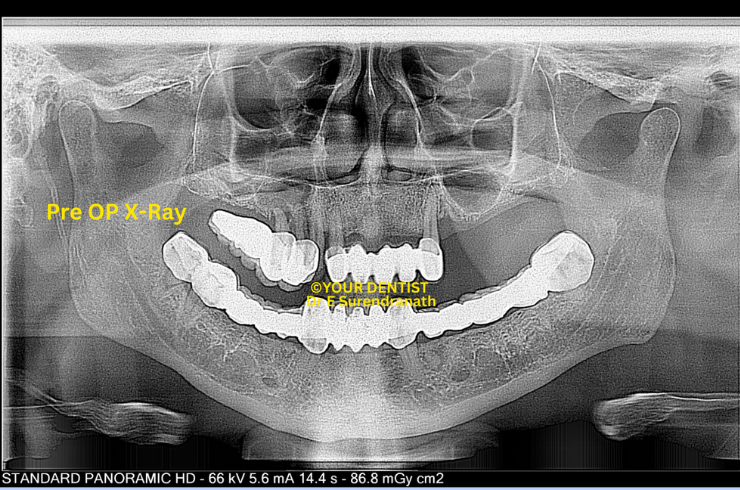

Basal & Cortical Implant - Pre OP X ray